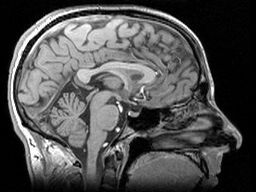

Cosa sono questi ‘cambiamenti’? Lo studio TRACK-HD sta conducendo un gran numero di misurazioni su ogni soggetto. La risonanza magnetica (MRI) cattura un’immagine tridimensionale dettagliata del cervello di ogni soggetto. I sintomi motori (movimento) vengono misurati in diversi modi, tra cui il tracciamento oculare ad alta tecnologia e altri strumenti sofisticati. Una serie di test sono progettati per testare la funzione intellettuale (o ‘cognitiva’) dei soggetti e il loro benessere emotivo. Infine, ci sono una serie di scale di valutazione che sono state utilizzate dai medici per valutare i segni dell’HD, e anche queste sono state misurate, consentendo agli scienziati di TRACK-HD di confrontare le loro informazioni con studi più vecchi. Si tratta di molti test e i partecipanti a TRACK-HD dovrebbero essere congratulati per il loro contributo all’intera comunità HD.

Misure più sensibili

Avere i dati al basale per ogni soggetto ha permesso agli scienziati di TRACK-HD di esaminare il cambiamento di ogni misurazione nel corso del primo anno. Delle dozzine di misurazioni effettuate, quelle derivate dall’imaging cerebrale sono state le più sensibili. Analizzare i cambiamenti in centinaia di immagini tridimensionali è difficile, quindi gli scienziati di TRACK-HD hanno utilizzato tre tecniche completamente distinte per assicurarsi che i cambiamenti osservati non fossero dovuti a problemi tecnici. Le risposte che hanno ricevuto da ogni tecnica concordavano molto bene tra loro, dandoci la certezza che stiano misurando cambiamenti reali nel cervello.

Il volume dell’intero cervello diminuisce più velocemente nelle persone portatrici della mutazione HD, anche se si restringe anche nel corso di un anno nelle persone senza la mutazione HD. Regioni specifiche del cervello che sono note per essere molto sensibili all’HD, chiamate caudato e putamen, sono degenerate ancora più velocemente nelle persone portatrici della mutazione HD. Lo studio ha anche riscontrato perdite precoci della materia bianca del cervello, che è una cosa importante perché è il ‘cablaggio’ del cervello.